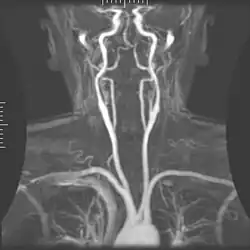

Angiografia

A angiografia por ressonância magnética (MRA) gera imagens das artérias para avaliá-las para estenose (estreitamento anormal) ou aneurismas (dilatação da parede vascular, em risco de ruptura). O MRA é frequentemente usado para avaliar as artérias do pescoço e do cérebro, a aorta torácica e abdominal, as artérias renais e as pernas (chamado de "escorrer"). Uma variedade de técnicas podem ser usadas para gerar as imagens, como a administração de um agente de contraste paramagnético (gadolínio) ou usando uma técnica conhecida como "aprimoramento relacionado ao fluxo" (por exemplo, sequências de tempo de voo 2D e 3D), onde a maior parte do sinal em uma imagem é devido ao sangue que recentemente se mudou para esse plano. As técnicas que envolvem acumulação de fase (conhecida como angiografia por contraste de fase) também podem ser usadas para gerar mapas de velocidade de fluxo com facilidade e precisão. A venografia por ressonância magnética (MRV) é um procedimento similar que é usado para imagens de veias. Neste método, o tecido agora está excitado inferiormente, enquanto o sinal é recolhido no plano imediatamente superior ao plano de excitação - criando assim o sangue venoso que recentemente se moveu do plano excitado.[52]

| Angiografia e venografia por Ressonância Magnética (MRA) | Voo de tempo | TOF | O sangue que entra na área de imagem ainda não está saturado magneticamente, dando um sinal muito mais alto ao usar tempo de eco curto e compensação de fluxo. | Detecção de aneurisma, estenose ou dissecção.[89] | ![]() |

| Ressonância magnética com contraste de fase | PC-MRA | Dois gradientes com magnitude igual, mas direção oposta, são usados para codificar uma mudança de fase, que é proporcional à velocidade das rotações.[90] | Detecção de aneurisma, estenose ou dissecção.[91] | ![]() |